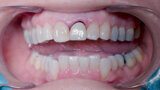

Fig. 27: Temporary crown seated and polished.

Fig. 28: Temporary crown one week post-op.